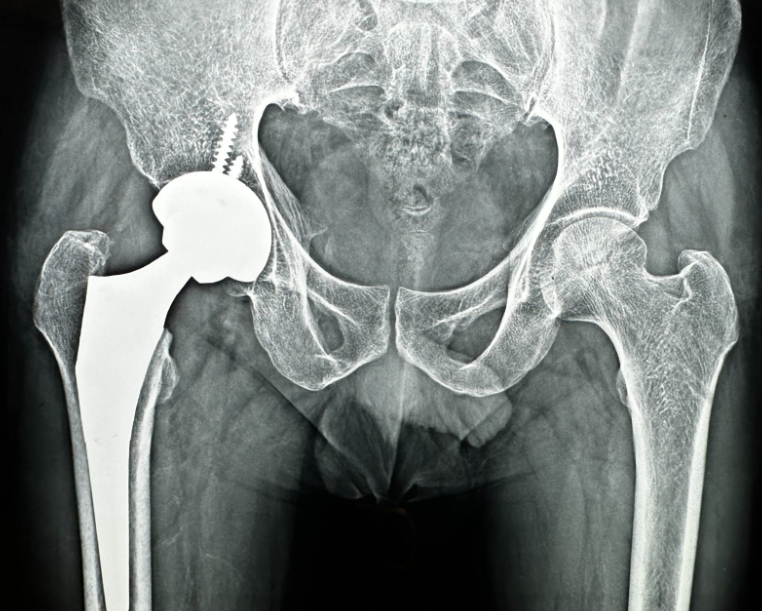

Hip Replacement Surgery in Nagpur – When Walking Should Not Hurt

Hip Replacement Surgery is often considered when hip pain starts interfering with simple activities like walking, sitting, or sleeping. Many patients reach this stage after months or years of managing discomfort, hoping it will improve on its own. But persistent hip pain can slowly limit independence and quality of life.

At Phoenix Orthopedic Superspecialty Hospital, Nagpur, hip replacement is approached with careful evaluation and patient education. Surgery is recommended only when non-surgical options no longer provide relief. The process focuses on restoring movement, reducing pain, and helping patients return to daily activities safely.

Modern hip replacement techniques have improved recovery times and outcomes. Patients often worry about mobility after surgery, but with proper rehabilitation and guidance, many regain stable and comfortable movement. The key lies in understanding expectations clearly, what recovery looks like, how physiotherapy helps, and how daily habits support long-term joint health.